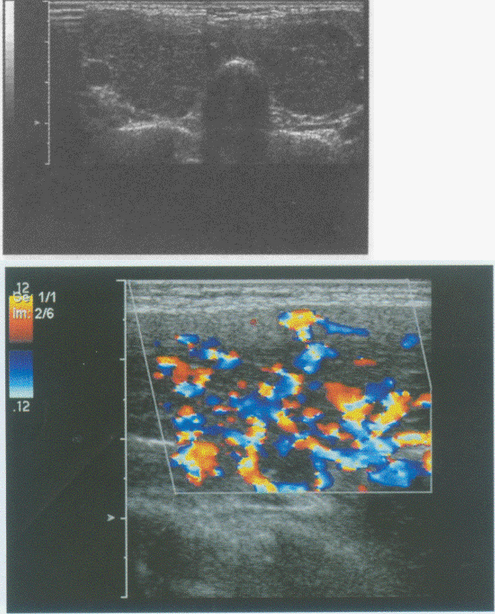

176、单项选择题

临床资料:女性,25岁,自述心悸,多汗,食欲亢进,体重减轻6个月余,发现颈部增粗1周。临床物理检查:甲状腺对称性增大,随吞咽上下运动,听诊有血管杂音。超声综合描述:双侧甲状腺增大,回声减低,明显不均,内未见囊实性肿物,CDFI:内可见丰富动静脉血流信号,呈"火海"征。见下图及彩图。

超声提示()。

A.结节性甲状腺肿

B.毒性甲状腺肿(原发性甲状腺功能亢进)

C.甲状腺腺瘤

D.甲状腺正常声像图

177、单项选择题